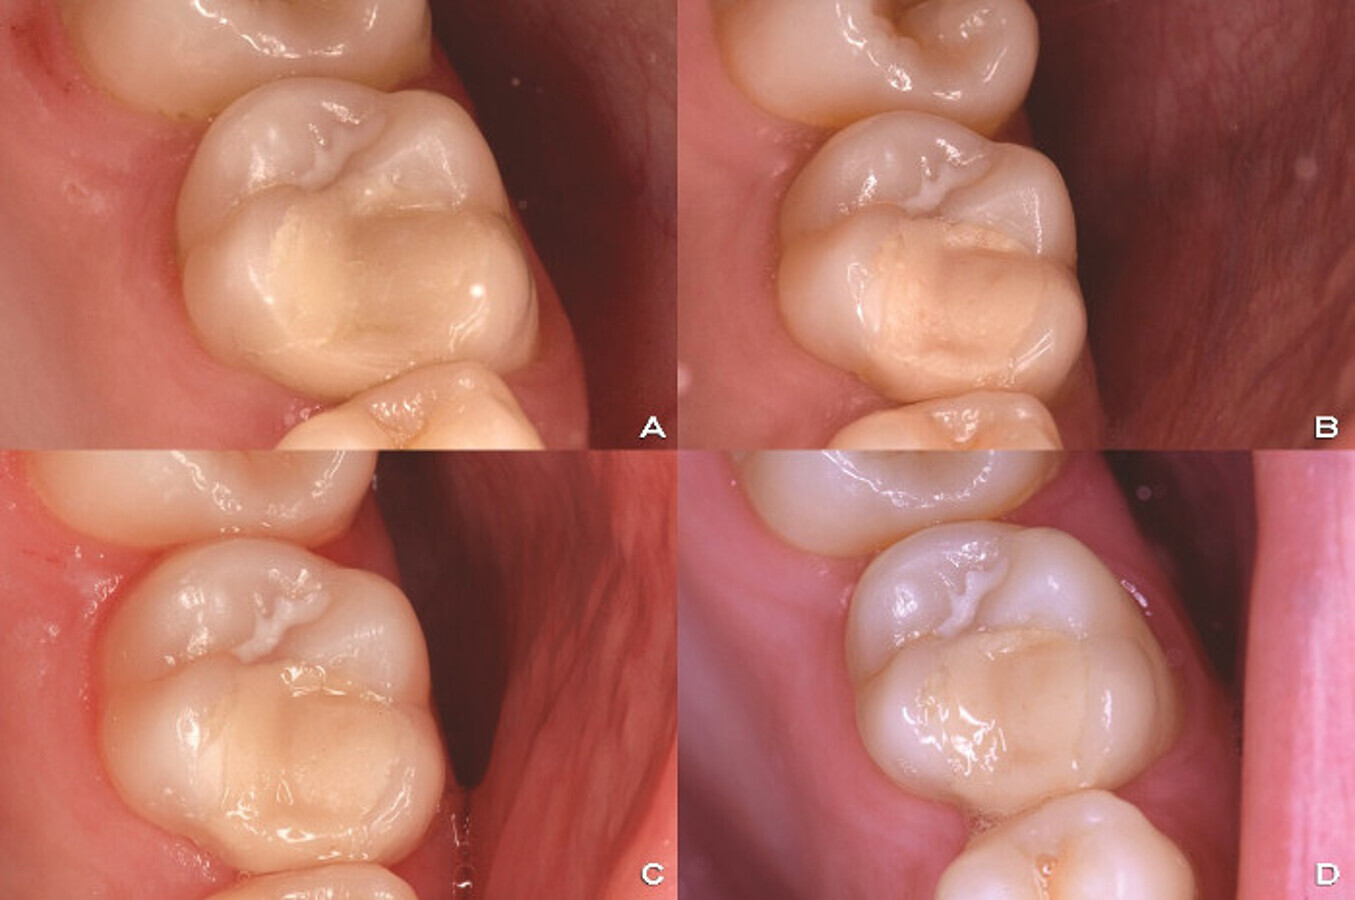

Restoration with glass hybrid EQUIA Forte. After the placement (A), 1–year recall (B), 2–year recall (C) and 3–year recall (D). (Image: Ivana Miletić)

In your webinar, you will speak about the clinical use of glass hybrids. What has been your personal experience with the material? Ever since I started working as a clinician, I have used a glass ionomer-based material regularly, almost daily, owing especially to its chemical adhesion to hard dental tissue and its bioactivity. Naturally, I have always paid close attention to every new improvement of the glass ionomer-based material, and of course, when glass hybrid technology was introduced about five years ago, I was among the first clinicians to use it in my country. This technology has improved the way I work. Furthermore, I am very satisfied with the functional and aesthetic results, and so are my patients.

To what extent is it a minimally invasive material? Glass hybrids are clearly minimally invasive materials because, as a long-term restorative material, they offer the unique opportunity to remove only soft and infected dentine and achieve sufficient and strong chemical bonding to demineralised dentine. Furthermore, the battery effect of the material, releasing and recharging with fluoride ions, provides protection, especially in patients with a high risk of caries occurrence, and healing in very deep carious lesions.